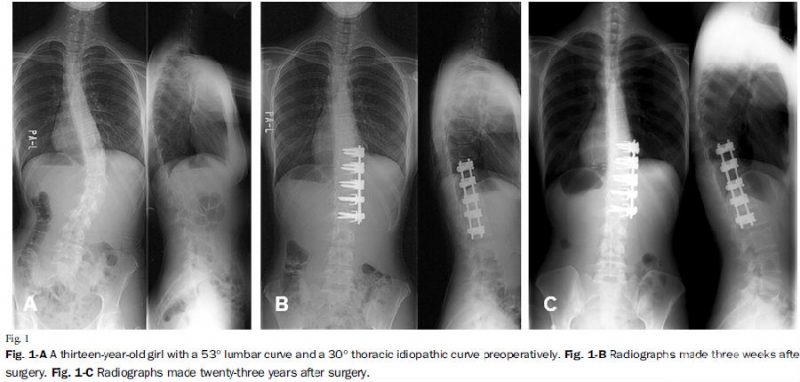

在另一篇发表在《THE JOURNAL OF BONE AND JOINT SURGERY》上对31名行前路手术的胸腰段/腰段AIS患者随访长达17.2年(12-23年)的研究中,Hideki S等人发现在影像学表现、肺功能和临床指标上前路矫正术均能获得令人满意的结果,前路双棒内固定矫正技术仍然是Lenke 5C型AIS的有效手术治疗方法[7]。

图6.引文7原文信息

图7. Lenke 5C型AIS患者前路术后矫正效果满意,随访23年无明显进展

7. Sudo H, Ito M, Kaneda K, Shono Y, Abumi K (2013) Long-term outcomes of anterior dual-rod instrumentation for thoracolumbar and lumbar curves in adolescent idiopathic scoliosis: a twelve to twenty-three-year follow-up study. J Bone Joint Surg Am 95:e49. doi: 10.2106/jbjs.L.00781